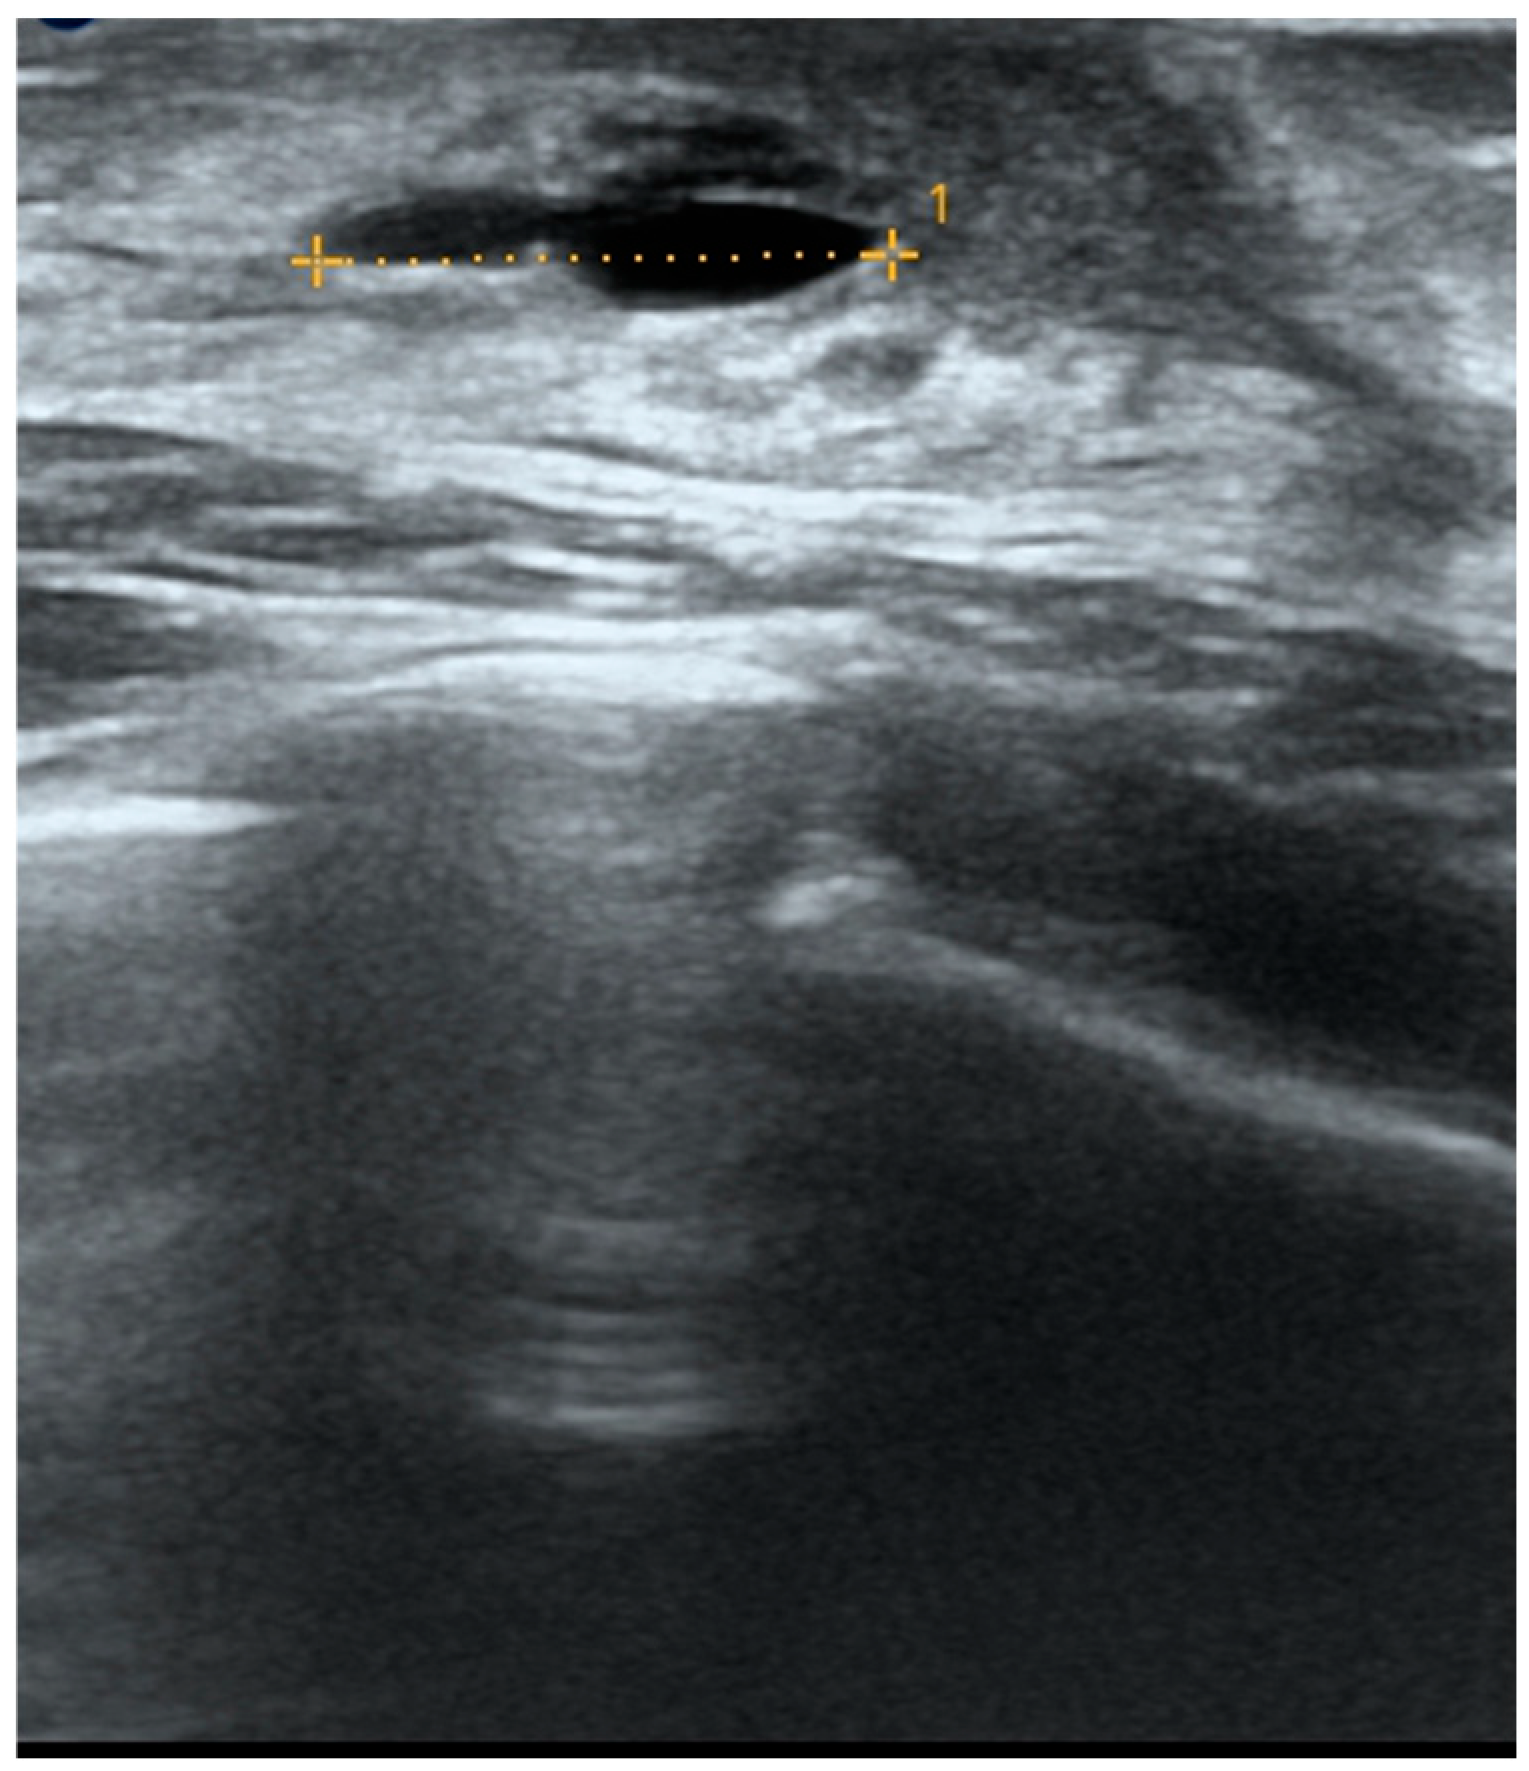

| Retroareolar cysts | Superficial, soft, smooth and bluish lesions | Homogeneous, unstructured greenish discoloration with blurred edges | Anechoic, oval, thin-walled mass with posterior enhancement; no Doppler flow | Prepuberal age |